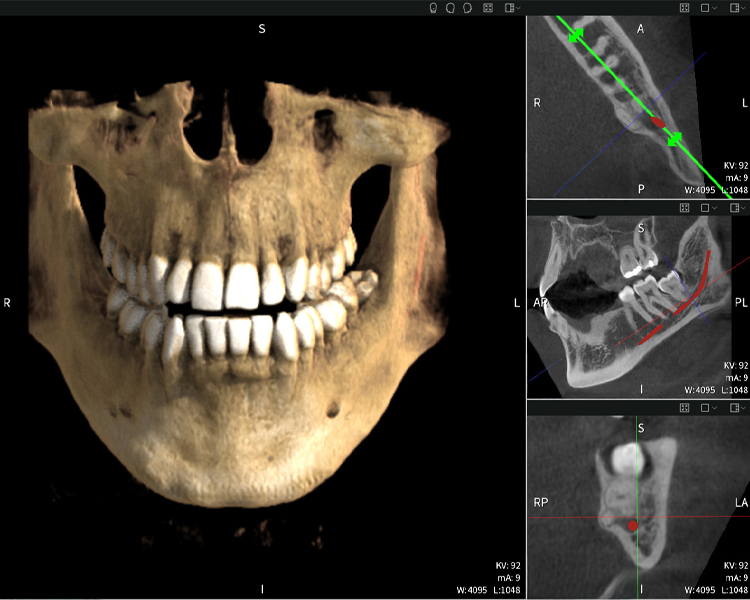

Figures b–d show various views of a 3D reconstruction of the mandible, providing a comprehensive overview of the mandibular anatomy, the position of the nerves in relation to the teeth, and allowing assessment of tooth symmetry and alignment.

Figure d shows the previously treated tooth 48, with its crown removed, and its roots left in proximity to the nerve, illustrating the high risk of nerve damage.